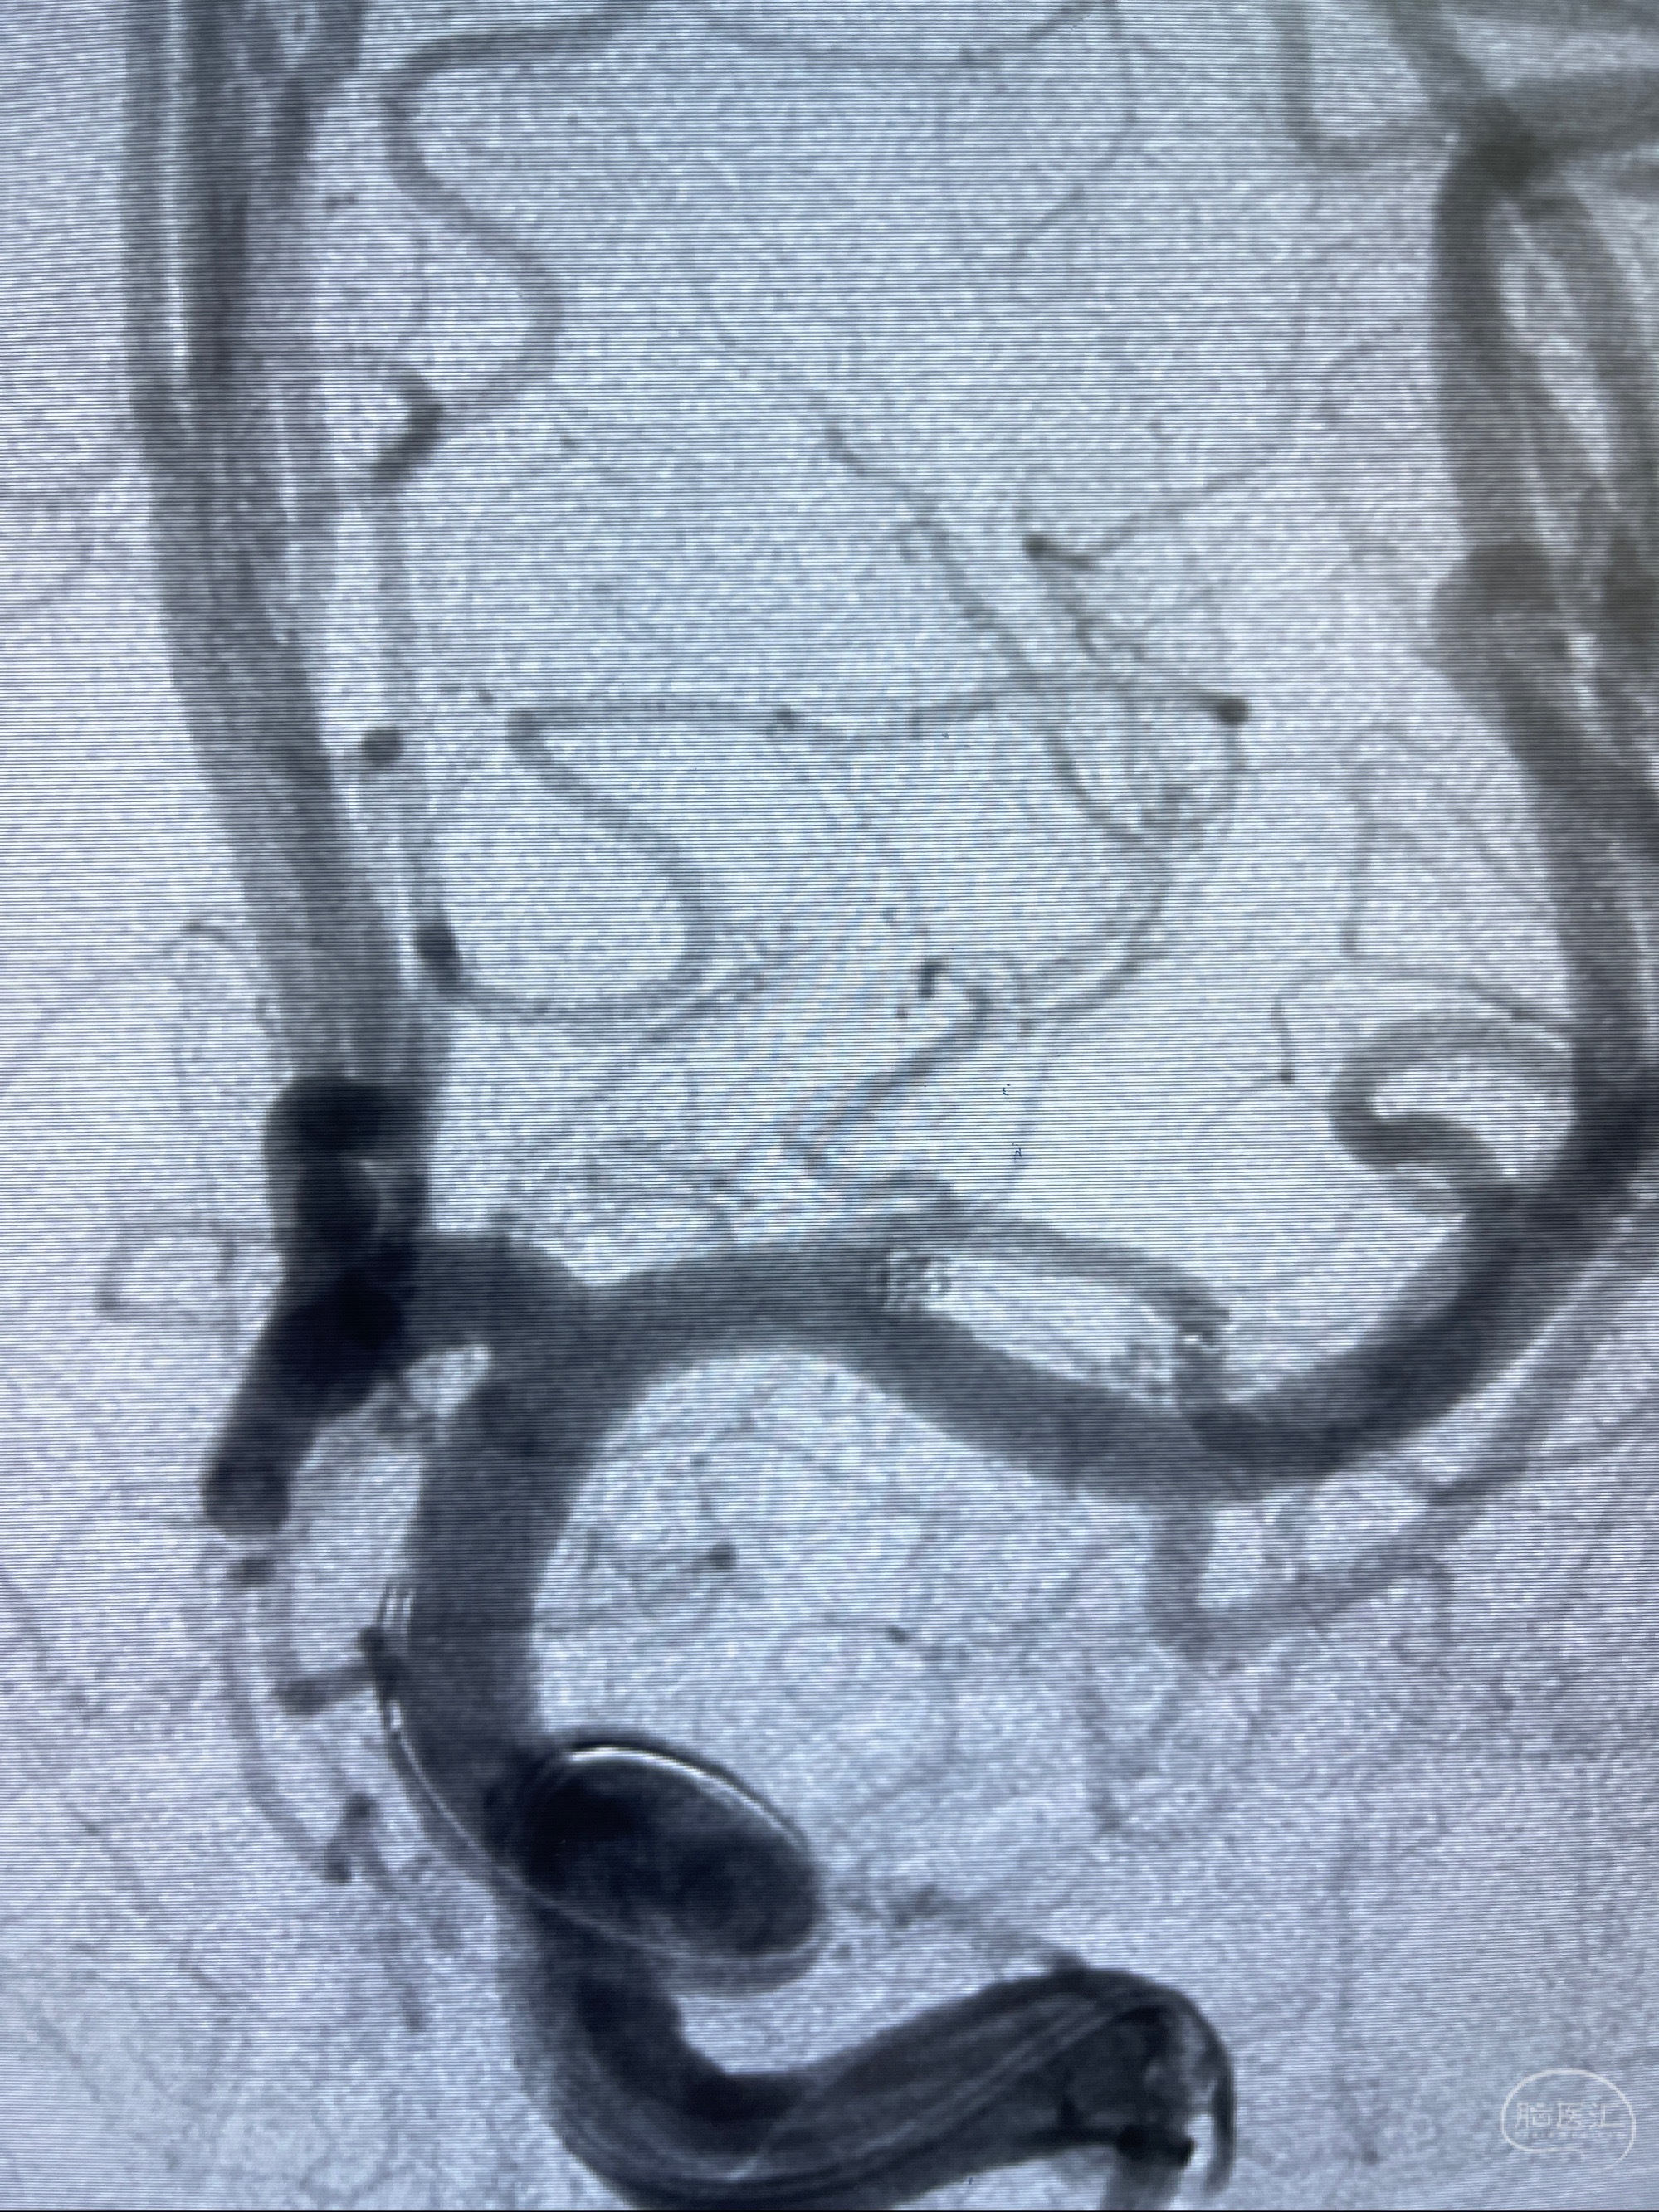

2023-08-14DSA:

左侧大脑中动脉动脉瘤,约2.6-2.8-3.4-2mm大小(瘤颈部、瘤体部、瘤高)